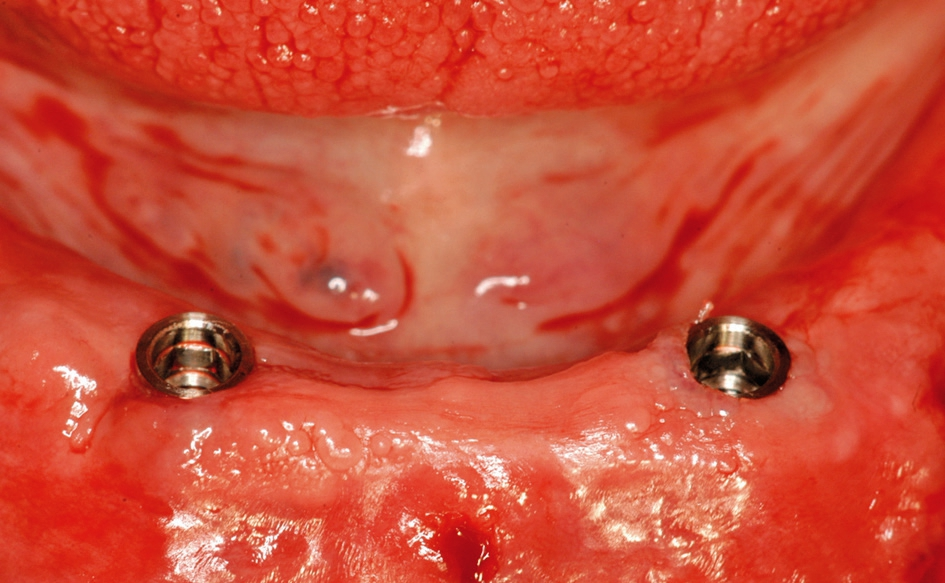

Abb. 1: Ein ausreichend dimensionierter, breiter Kieferkamm ist vorteilhaft für die Behandlung.